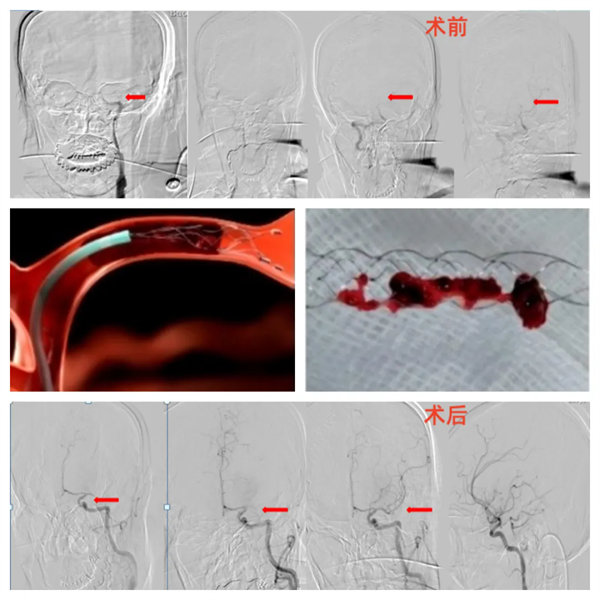

②取栓治療

針對顱內大血管閉塞。通過導管經血管內到達閉塞部位,使用特殊的取栓裝置將血栓取出,恢復閉塞部位血流。取栓治療的最佳時間為發病6小時以內,部分患者可延長至24小時以內。

急性出血性卒中包括腦出血或蛛網膜下腔出血,一旦確診,往往需要積極尋找并盡可能消除病因,同時進行降顱壓治療,必要時需急診手術,其中因動脈瘤破裂引起的蛛網膜下腔出血可以急診行動脈瘤栓塞治療。